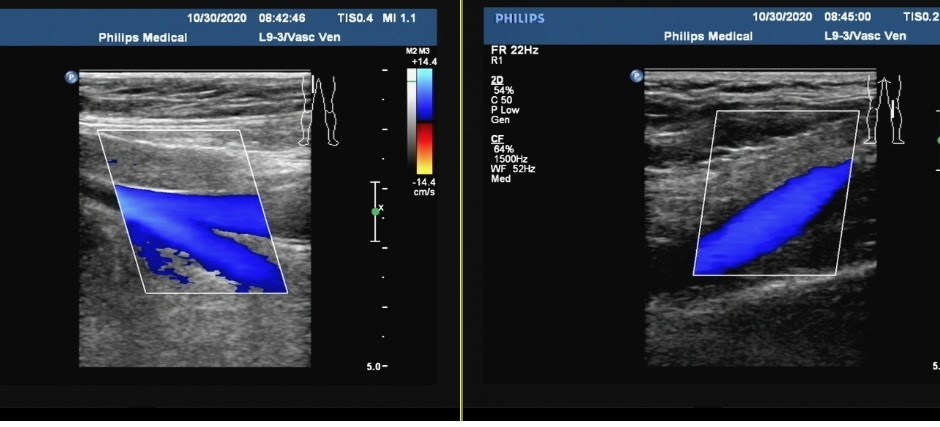

双下肢动脉硬化;双下肢深静脉未见明显血栓(图1)。

图1:超声